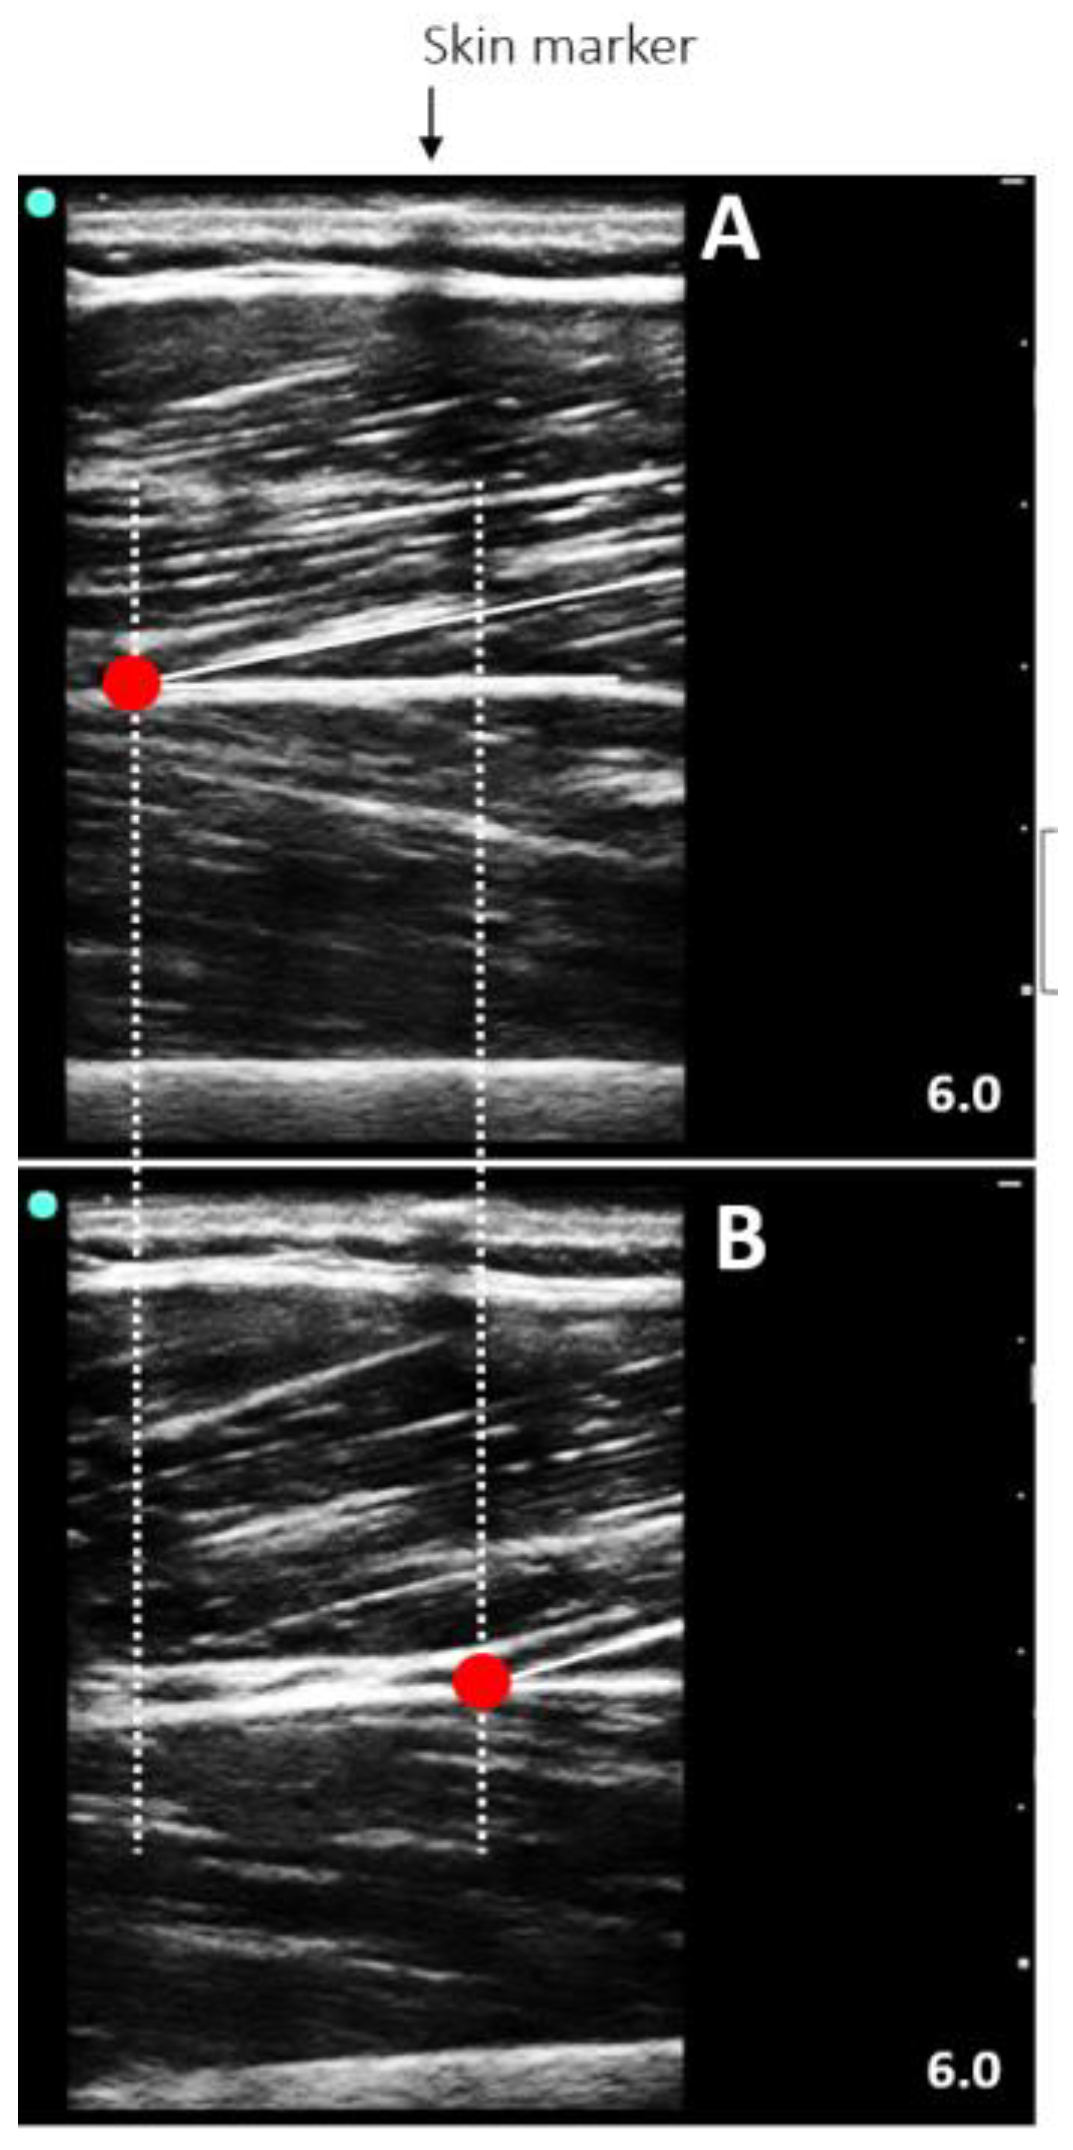

2.5.5. Patellar Tendon Properties

Mechanical Properties